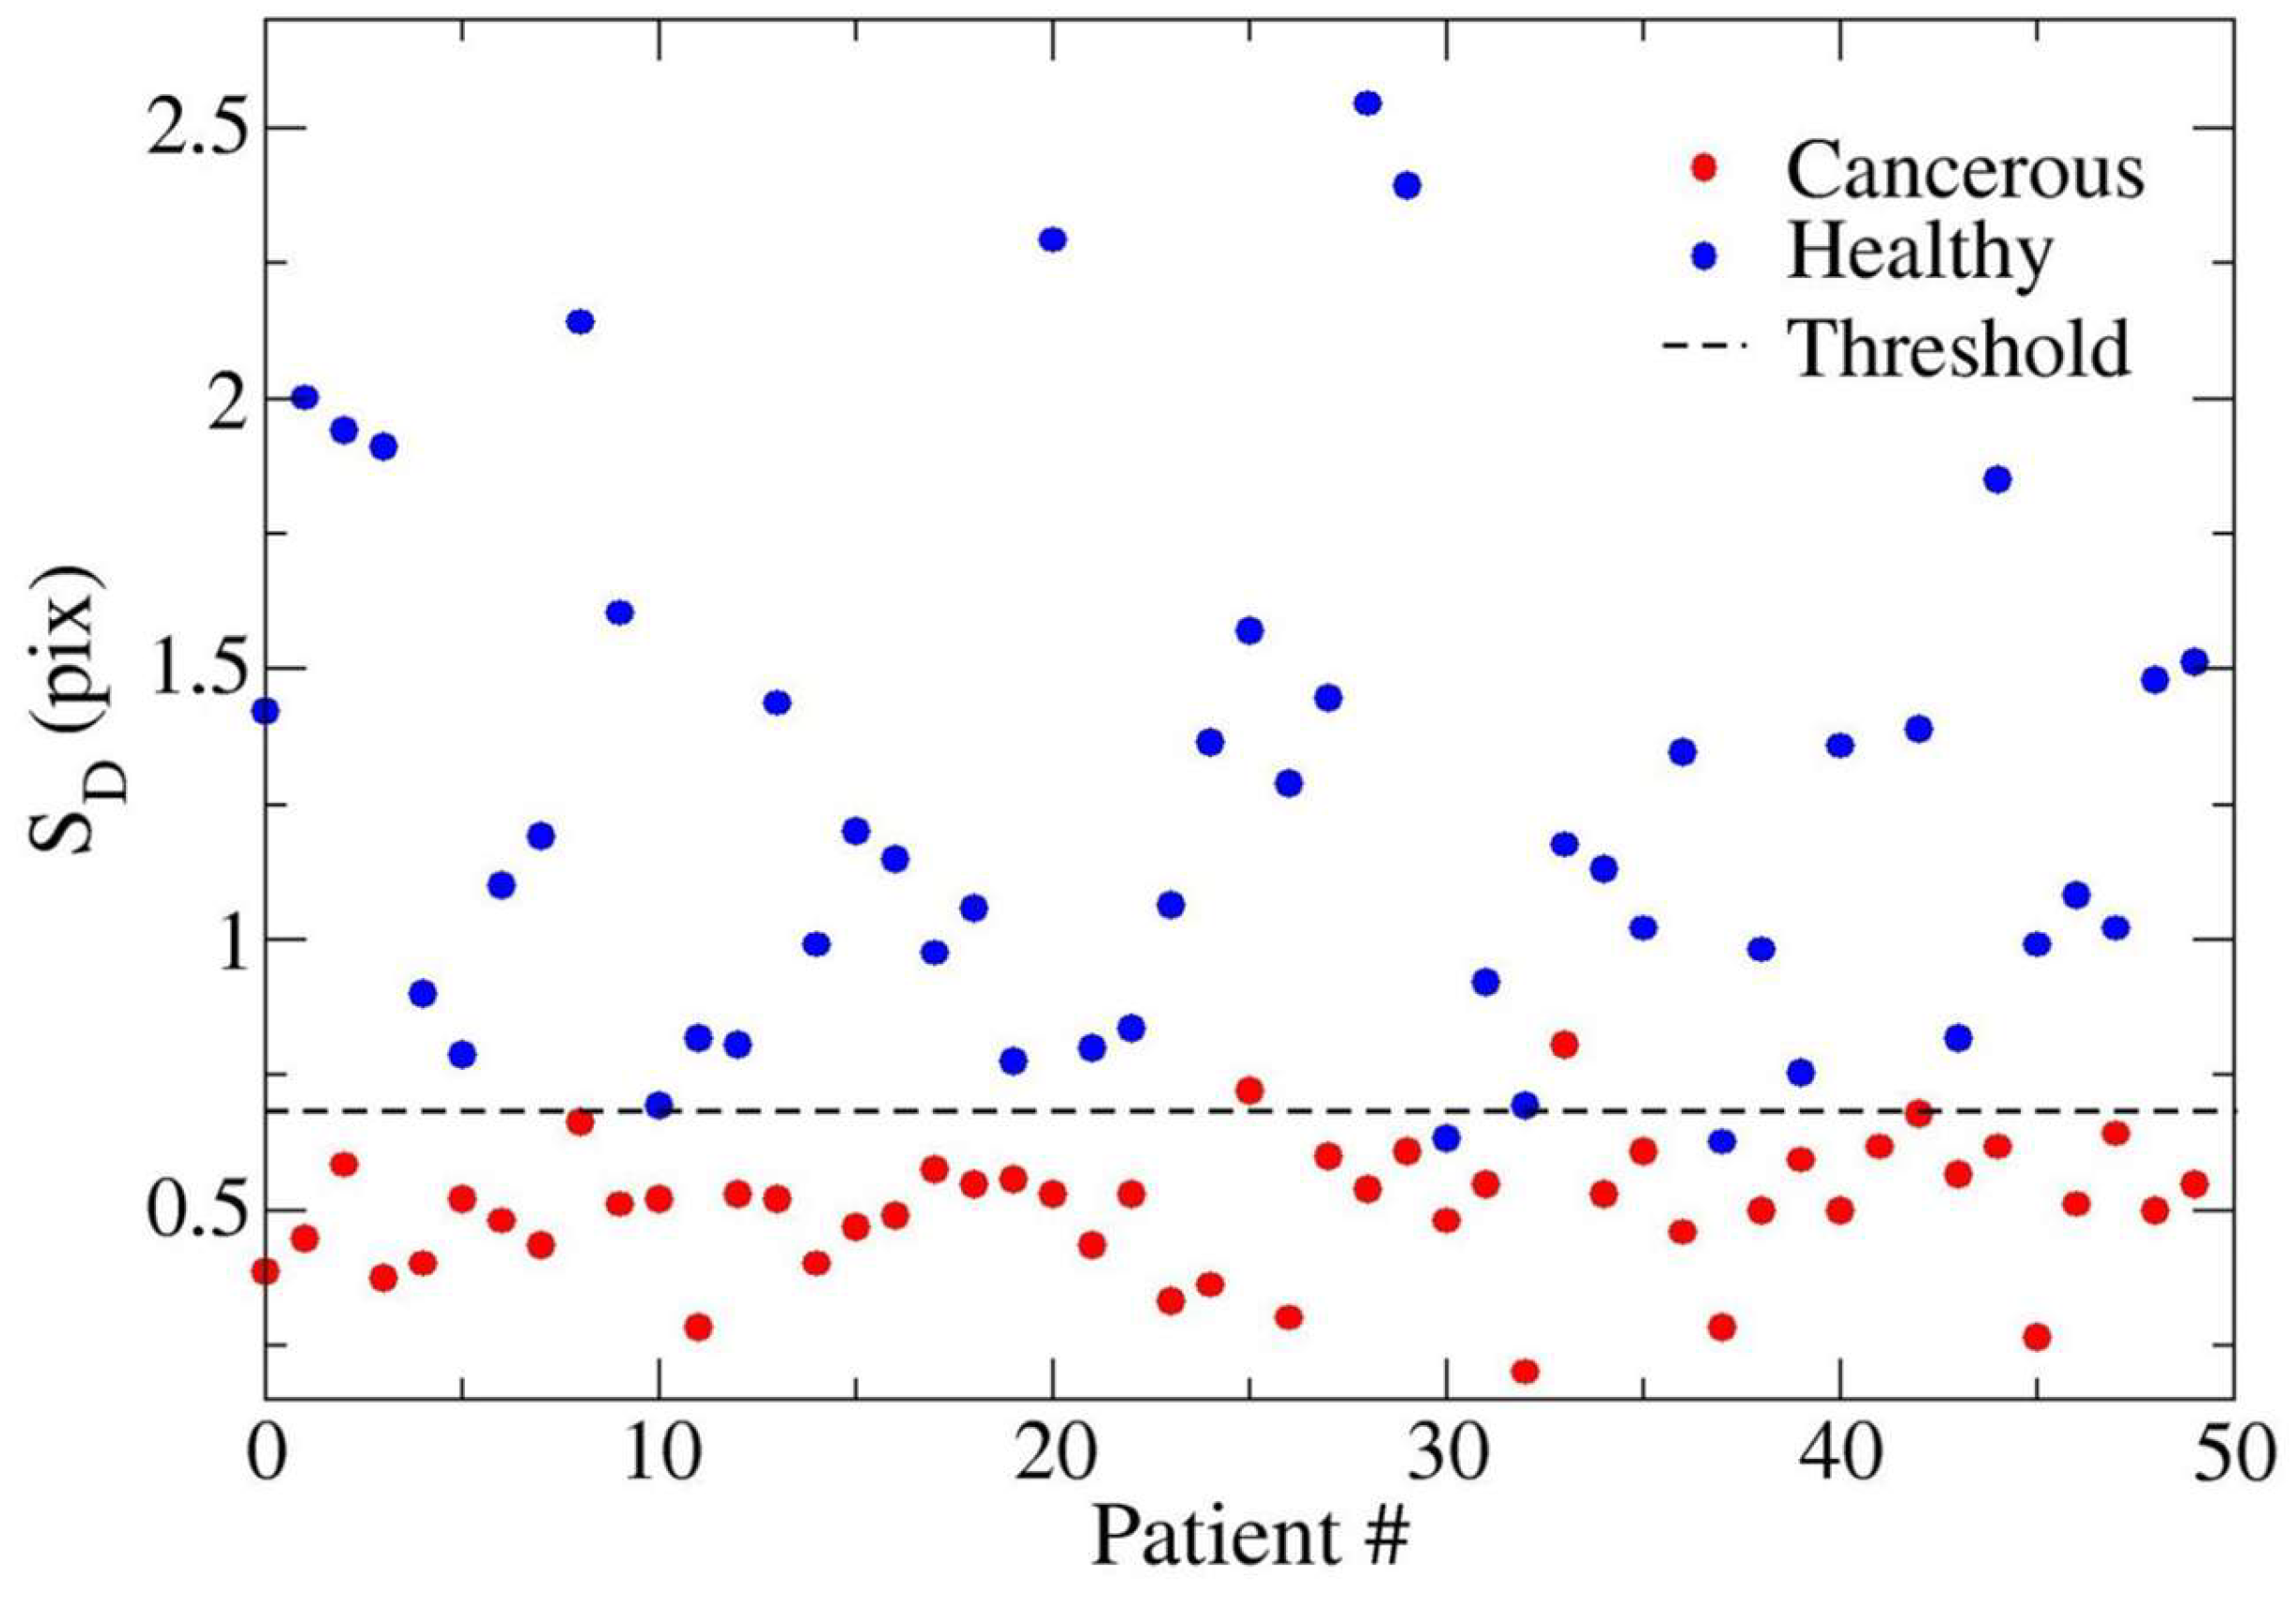

3. Results